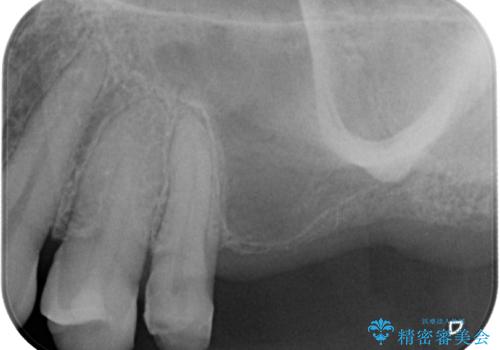

- 前歯の色が不揃いなことを気にして来院された患者様です。

右側の歯は根の先端部分の病変により歯肉から膿が出ていたため根管治療を行い、左側のむし歯が大きい2歯は神経が残っているので神経を残したまま、オールセラミッククラウンにて補綴することとしました。

根管治療により膿の出口は消え、オールセラミッククラウンにより前歯全体に統一感が出て、明るい口元の印象とすることができました。